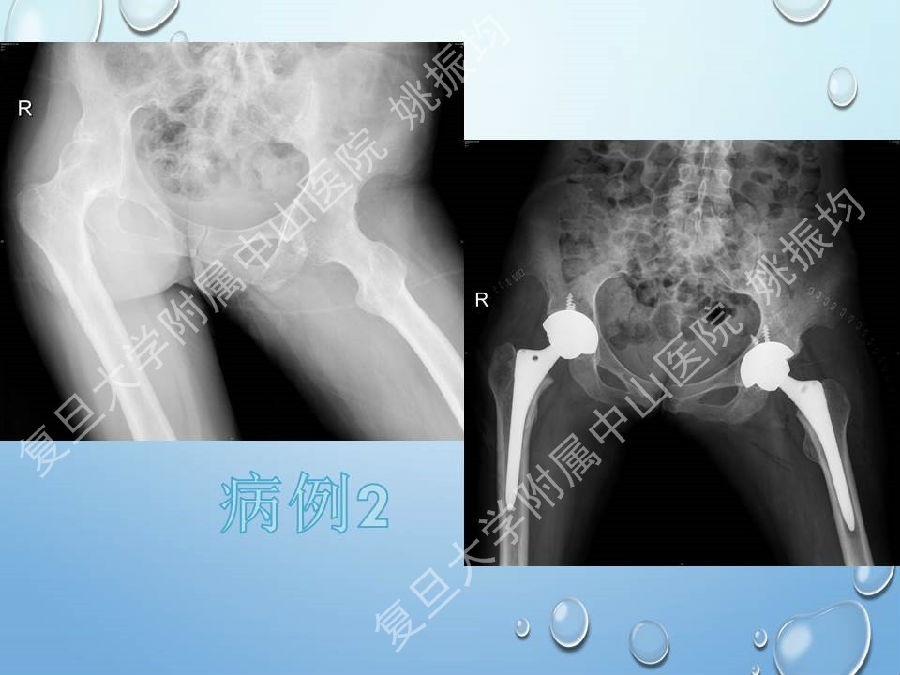

强直性脊柱炎(ankylosing spondylitis, AS)是一种血清学阴性的慢性进行性炎症性疾病,主要侵犯骶髂关节、脊柱和髋关节等。对AS晚期引起的髋关节畸形施行全髋关节置换术,是目前公认的改善关节功能的有效方法.

复旦大学附属中山医院姚振均教授在“强直髋关节的人工关节置换”专题授课中从强直性脊柱炎的患者选择、术前准备、手术技巧、术后护理、病情转归、典型病例分享方面,讲述了他是如何做强制髋关节置换手术的,我们一起来回顾下精彩课件吧!